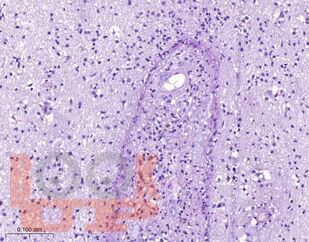

Учебное пособие посвящено актуальным вопросам патогенеза, клинического течения, диагностики и лечения церебрального токсоплазмоза у ВИЧ-инфицированных пациентов. Особое внимание уделено вопросам дифференциальной диагностики церебрального токсоплазмоза от другой патологии нервной системы, в том числе опухолей головного мозга, нарушений мозгового кровообращения, воспалительных заболеваний. В пособии представлены собственные клинические наблюдения многоочаговых и солитарных форм церебрального токсоплазмоза.